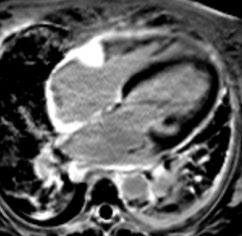

Gastric GIST shows an intermediate pattern of enhancement, while small bowel GIST shows marked arterial phase enhancement. ‘Tumour vessel’ sign, a feature of small bowel GIST due to early venous return and prominence of the draining vein, helps in tracing the origin of the tumour. A nodule within the mass is a sign of recurrence.1 Treatment of choice for resectable GIST is surgery, although neoadjuvant imatinib is given to reduce the tumour size, and postsurgery imatinib is administered to prevent recurrence of the disease for at least 3 years. In case of metastasis or recurrence, imatinib is a first line drug.4,10,11,20

CONCLUSION

Although CT is the modality of choice for GIST, it is imperative for a radiologist to be wellacquainted with various other non-cross section imaging, such as radiographs, small bowel series, and ultrasound, to increase the level of confidence in radiological diagnosis before histopathology and immunohistochemistry confirms it.

Creative Commons Attribution-Non Commercial 4.0 ● April 2024 ● Radiology 91 Case Report

References

1. Inoue A et al. Gastrointestinal stromal tumors: a comprehensive radiological review. Jpn J Radiol. 2022;40(11):1105-20.

2. Levy AD et al. Gastrointestinal stromal tumors: radiologic features with pathologic correlation. Radiographics. 2003;23(2):283304.